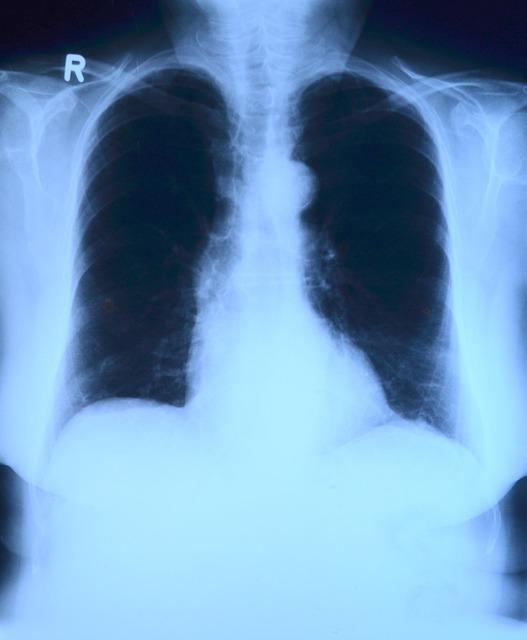

篩查肺癌,CT 不如做胸片?

一提起胸部 CT 或 X 線檢查,很多人就會想到輻射!于是經(jīng)常出現(xiàn)這樣的情況,醫(yī)生檢查時發(fā)現(xiàn)了可疑的情況,一建議做個胸部 CT,就有人會不解地問:“我又不咳嗽、不胸痛的,做 CT 干啥,還有輻射呢?”

這還真不是醫(yī)生沒事找事,肺癌臨床表現(xiàn)多種多樣,早期通常沒有癥狀或癥狀不明顯,初診時 75%的患者已發(fā)展為晚期肺癌,早期肺癌只有在胸部 CT 掃描或高危人群篩查時才會被發(fā)現(xiàn)。

至于那些怕輻射的朋友大可放心,其實(shí)人體一年接受正常自然環(huán)境下的輻射劑量為 3~4mSv;一次胸片輻射劑量為 0.2~1.2mSv,一次胸部普通螺旋 CT 輻射劑量為 3~5mSv,相當(dāng)于暴露在自然環(huán)境下 1 年。

結(jié)論:肺癌高危人群篩查早期肺癌,多個國內(nèi)外指南均推薦低劑量 CT 平掃為首選。平時體檢、診療檢查時,偶爾做一次 CT,并不會損傷身體。備孕、已孕、哺乳期女性受檢者,應(yīng)在檢查前告知醫(yī)生,孕期女性應(yīng)避免做 CT 檢查。